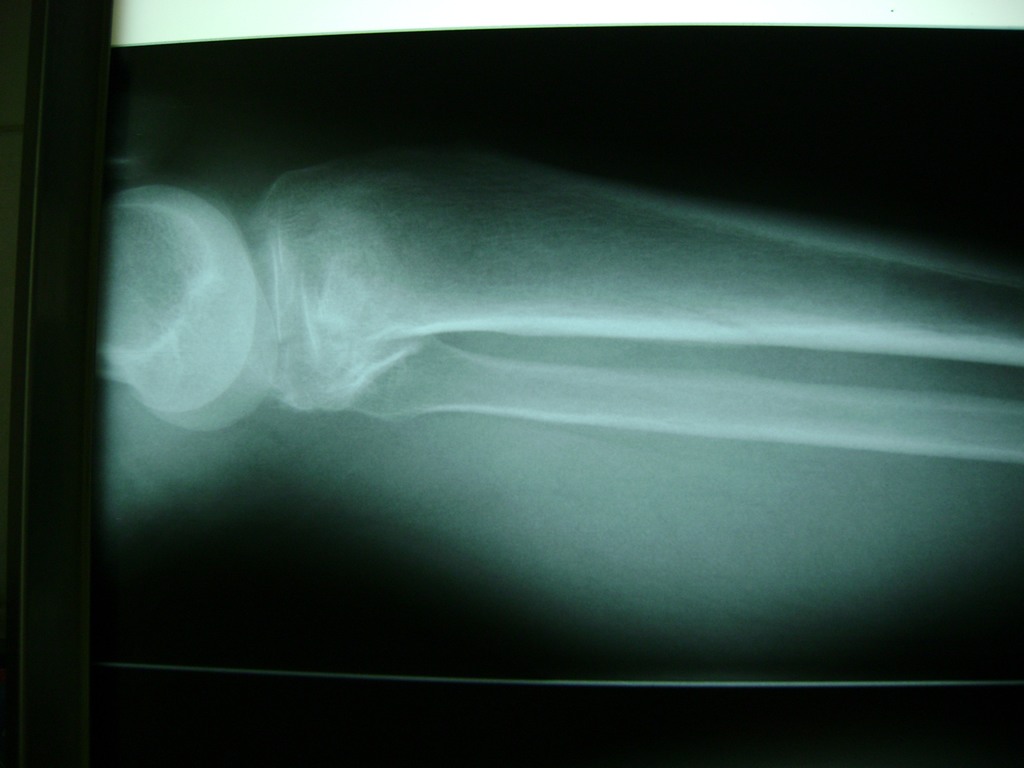

Cirugía de Tibia y Peroné

La artroscopia de rodilla es un cirugía en el cual la estructura interna de la articulación es examinada ya sea para realizar un diagnostico o para realizar un tratamiento, este procedimiento se realiza utilizando un instrumento parecido a un pequeño tubo llamado artroscopio.